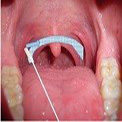

Streichen sie unter leichten Drehbewegungen des Tupfers halbkreisförmig über das im Bild markierte Areal. Bild 3 - Führen Sie nun den Tupfer ca. 2 cm tief in die Nase ein und nehmen Sie durch 3 Drehungen an der Naseninnenwand etwas Nasensekret ab. Bild 4

Bild 3